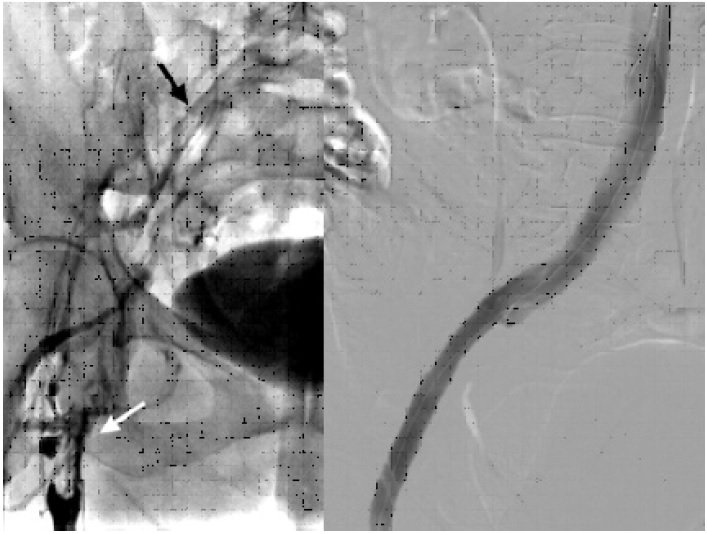

Mujer de 55 años, previamente sana, que consulta por cuadro de edema marcado de todo el miembro inferior izquierdo, con dolor incapacitante, coloración azulada-violácea del miembro y parestesias en el pie, que comenzó una semana previa a la consulta y que fue empeorando al punto de inhabilitar la marcha. Al examen físico era notable el edema desde el pie hasta la raíz del muslo, tenso, así como la ausencia de pulsos distales con solo señales monofásicas por Doppler sin alteración de la función motora. El eco Doppler reveló una TVP que involucraba las venas femoral común, femoral proximal y femoral profunda, y también la vena safena magna, por lo que se decidió iniciar de inmediato anticoagulación con heparina de bajo peso molecular. La angiotomografía mostró una extensa TVP desde la vena ilíaca externa izquierda proximal hasta la vena poplítea, al igual que una bifurcación aórtica retrocava, con compresión a nivel de la confluencia de las venas ilíacas externa e interna, entre el sacro y la arteria hipogástrica izquierda (Figura 1).

Se decidió llevar a la paciente a Hemodinamia para colocación de un filtro de vena cava inferior (VCI) por vía femoral derecha. Luego, con la paciente en decúbito ventral, se realizó una punción guiada por ecografía de la vena poplítea con colocación de un introductor 11 French por medio del cual se llevó a cabo una trombectomía mecánica de toda la oclusión con dispositivo Aspirex®S. Un claro sitio de compresión se notó al mismo nivel observado en la angiotomografía, que ocasionaba incluso una ruptura parcial de la vena con fuga de contraste sin descompensación hemodinámica. Se decidió colocar un stent venoso autoexpandible de 12 × 120 mm, y dilatación con balón, con un resultado final muy satisfactorio (Figura 2).

Fig. 1 Izquierda. Corte axial de angiotomografía que evidencia bifurcación aórtica (flechas negras), por detrás de la confluencia iliocava (flecha blanca). Derecha. Corte sagital que objetiva compresión por la arteria hipogástrica izquierda (flecha negra) que causa trombosis de la vena ilíaca externa (flechas blancas).

Fig. 2 Izquierda. Flebografía inicial que muestra trombosis la desde vena femoral proximal (flecha blanca), que recanaliza con hipoflujo a nivel de vena ilíaca común (flecha negra). Derecha. Flebografía final post colocación de stent mostrando permeabilidad absoluta del eje ilíaco.